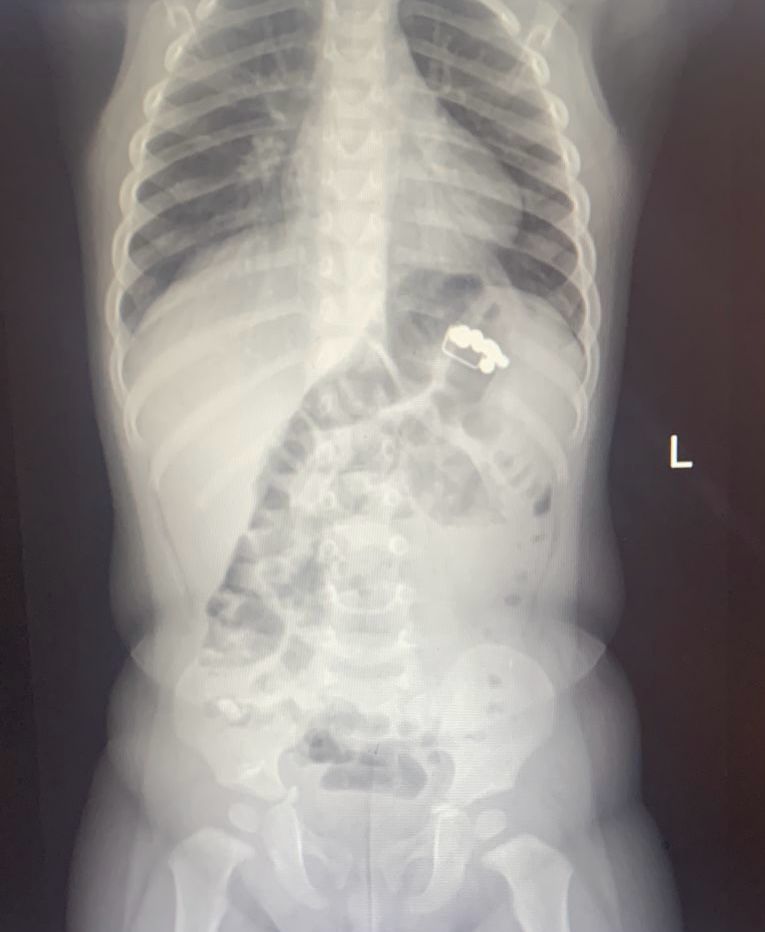

А сколько детей спасли воронежские медики! Малыши глотали магниты, канцелярские кнопки, гайки, монеты и батарейки. Все это (и не только) извлекали из маленьких пациентов в 2025 году.